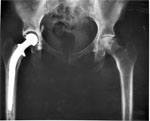

Эндопротезирование тазобедренного сустава является эффективным и экономически обоснованным методом лечения остеоартритов независимо от возраста, сообщают американские ученые

У людей с ожирением риск развития инфекционных осложнений и вывихов после повторной артропластики тазобедренного сустава гораздо выше.

Несмотря на то, что после замены сустава (артропластики) пожилым людям требуется несколько недель на восстановление, отдаленные результаты операции превосходят любые ожидания, сообщают ученые